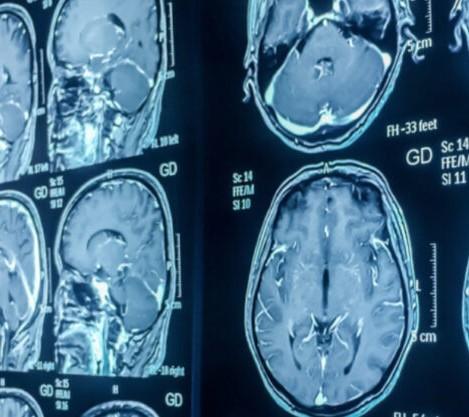

Welcome to our cutting-edge online

CBCT (Cone Beam Computed Tomography) reporting platform! We are dedicated to providing dental professionals with efficient and accurate interpretations of CBCT scans to aid in the diagnosis and treatment planning of dental conditions.

CBCT imaging offers high-resolution 3D visualization, providing detailed information for comprehensive diagnosis. Our radiologists are proficient in interpreting CBCT scans, enabling them to accurately analyze the dental and craniofacial structures.